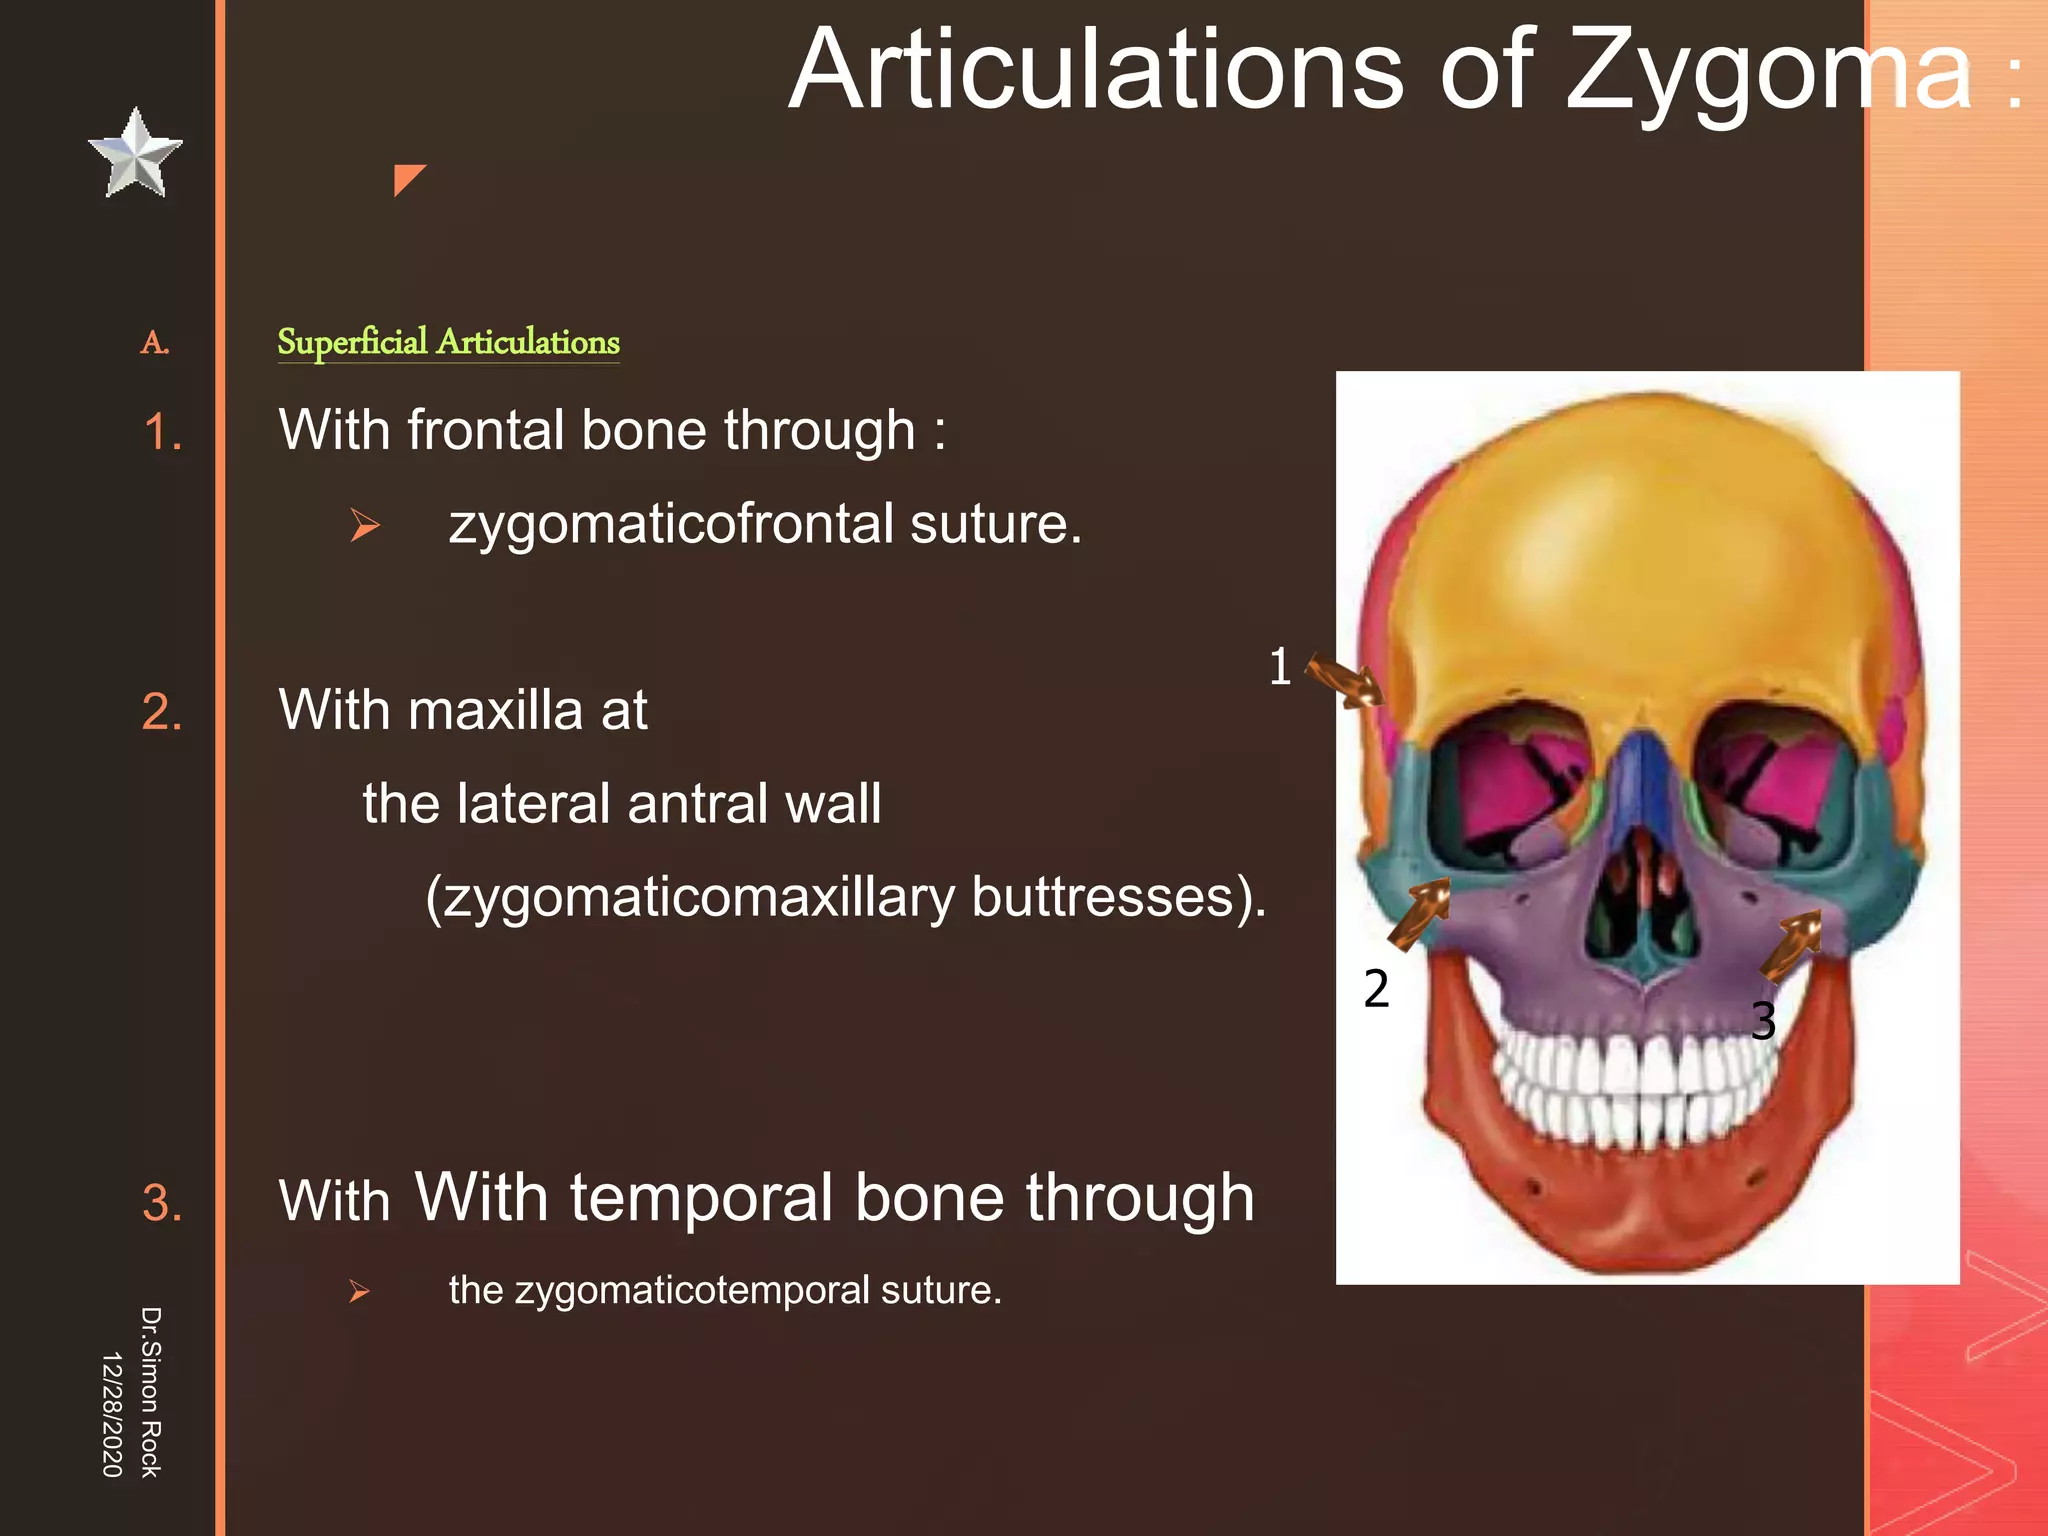

This document discusses the anatomy and fractures of the zygomatic bone. It notes that the zygoma forms the cheekbone and articulates with several other facial bones. Zygomatic fractures most commonly occur in the arch or body due to blunt trauma. Diagnosis involves checking for diplopia, ecchymosis, and other signs of orbital or facial bone involvement. Treatment may involve closed or open reduction based on the severity of displacement. Closed reduction techniques try to elevate the bone back into position without surgery, while open reduction requires surgical exposure and fixation of the fracture site.